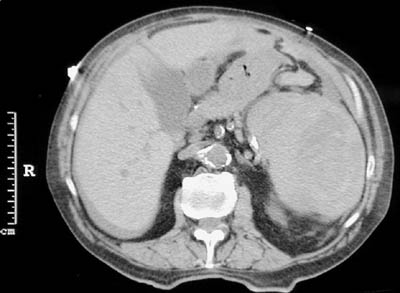

Seen on the left in this abdominal CT scan is an enlarged spleen with irregular intraparenchymal lucent areas representing hematoma formation following blunt trauma to the abdomen.